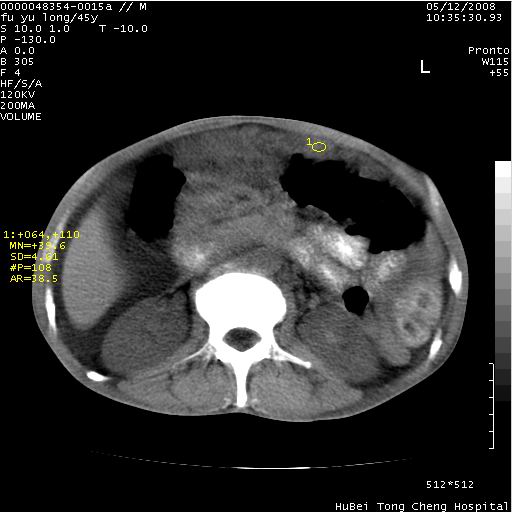

以下是引用医影拾贝在2008-5-30 2:38:00的发言:[br]气肿性胃炎、胃十二指肠溃疡、腹膜炎,考虑穿孔可能性较大

以下是引用lkc8963在2008-5-30 8:44:00的发言:[br]胃窦癌伴网膜(胃结肠韧带)/腹膜及腹膜后淋巴结转移.